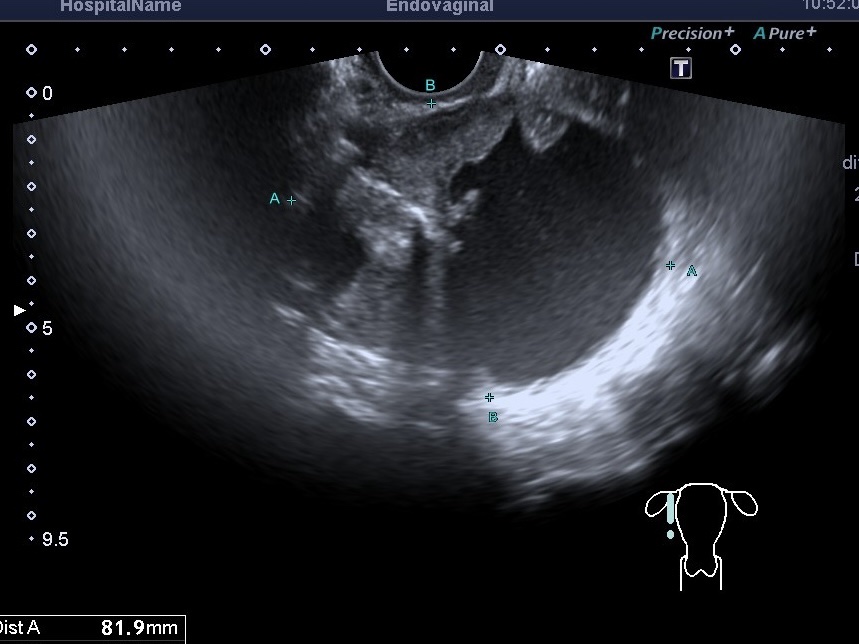

К примеру, к нам обратилась пациентка 65 лет с жалобами на непонятное снижение веса и тянущие боли в области малого таза. При проведении УЗИ малого таза было выявлено крупное кистозное образование яичника с пристеночными крупными солидными разрастаниями с повышенной васкуляризацией. Пациентка была направлена к онкологу-гинекологу, на КТ и МРТ для уточнения распространения процесса. Такие образования яичников чаще относятся к злокачественным опухолям. Лечение будет зависеть от стадии и вида опухоли. Чем раньше выявляется опухоль яичника, тем больше шансов на успешное лечение.